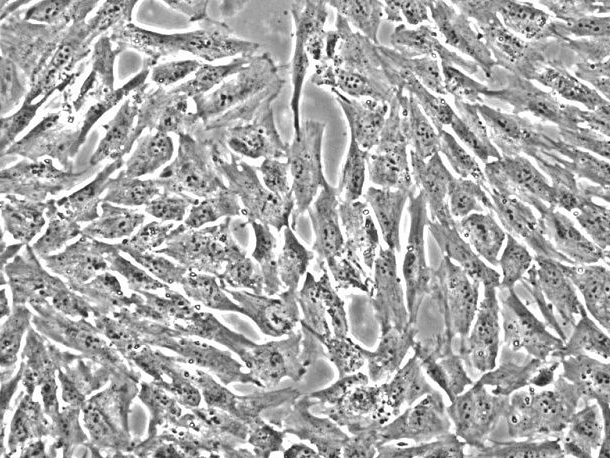

成纤维细胞样

别称:Wi-38; WI 38; WI38; Wistar Institute-38; AG06814-J; AG06814-M; AG06814-N

细胞形态:成纤维细胞样

背景描述:WI-38(人胚肺细胞)通过STR鉴定是来自妊娠3个月的正常胚胎肺组织。WI-38细胞是首株用于人类疫苗制备的人二倍体细胞系,培养液中添加TNF-α可以促进WI-38细胞生长。